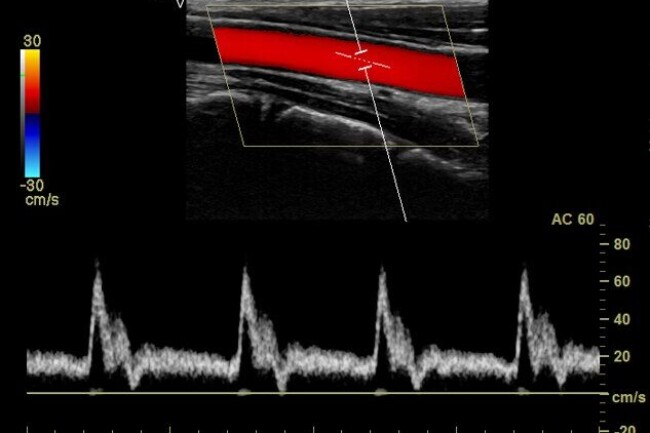

Esami ecografici a domicilio

con rilascio di referto ed immagini immediato